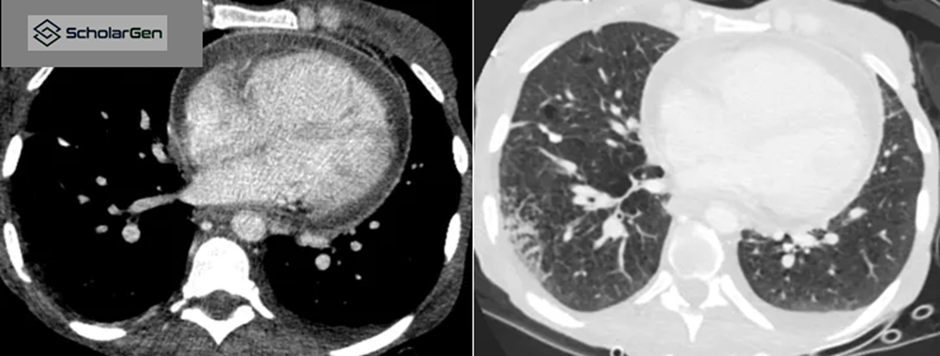

Figure 2. Axial CT showing moderate pericardial effusion, atelectasis, and paraseptal emphysema.

• Moderate pericardial effusion

• Centrilobular and paraseptal emphysema

• Associated segmental atelectasis

Answer: (4) All of the above

Explanation: The CT demonstrates pleural and pericardial involvement with additional lung abscesses, indicating severe infectious pathology.